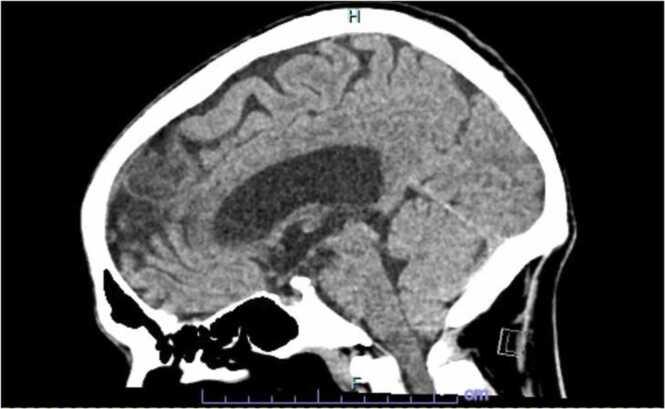

(previously known as ) infections are reportedly increasing in patients with implanted foreign material. Though it is a rare cause of bacterial endocarditis, patients with implanted prosthetic valves and devices have potential increased risk. Cutibacterium species are an ubiquitous environmental surface contaminant and typically difficult to culture, in case of high suspicion for infective endocarditis extended duration incubation of blood or any tissue sample and 16S RNA sequencing of any tissue sample is helpful for a microbiological identification. We report a case of a 50 year old male with culture negative prosthetic valve endocarditis in which the pathogen was identified by molecular testing 16S RNA gene sequencing.

据报道,(以前称为)植入异物的患者感染情况正在增加。虽然它是细菌性心内膜炎的罕见病因,但植入人工瓣膜和装置的患者潜在风险增加。痤疮丙酸杆菌是一种普遍存在的环境表面污染物,通常难以培养,在高度怀疑感染性心内膜炎的情况下,延长血液或任何组织样本的培养时间以及对任何组织样本进行16S RNA测序有助于微生物鉴定。我们报告一例50岁男性人工瓣膜心内膜炎培养阴性的病例,其中病原体通过分子检测16S RNA基因测序得以鉴定。